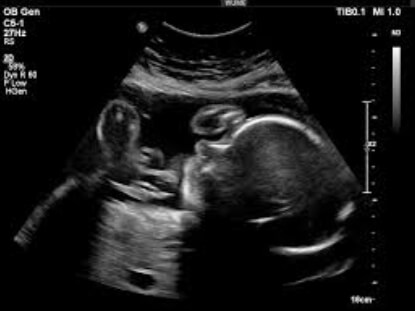

27 Haftalık Bebeğin Ultrason Görüntüsü

Öncelikle belirtmek isteriz ki bebeğinizin ultrason görüntüsünün internette karşılaştığınız bu fotoğraflardan ya da arkadaşlarınızın ultrason görüntülerinden oldukça farklı olması normaldir. Zaten zamanla gözlemleyeceğiniz gibi, artık bebeğiniz ultrason görüntüleri kendi içinde bile benzememeye başlayacak; çünkü bebeğiniz çok hareketli ve anne karnında yeterli alana da sahip olduğu için, onu her zaman istediğiniz pozisyonda yakalayamamanız normal.

• Ultrasonda bebeğinizin irkilir ya da hıçkırır gibi düzenli bir sarsılma hareketi yaptığını görebilirsiniz. Birçok ebeveyn bu durumdan endişelense de telaşlanacak bir şey yok: Bebeğiniz nefes alma egzersizleri yapıyor.

• Bebeğinizin tüm oksijen ihtiyacını plasenta yoluyla karşılamasına rağmen, amniyon sıvısını yutarak nefes alıp vermeye çalışması, ultrasondaki hıçkırığa neden oluyor.

• Bebeğinizin ultrason görüntüsündeki cılızlık da bu haftadan itibaren azalmaya başlayacak ve bebeğiniz tombullaşacaktır.

27 hafta gebelik ultrason